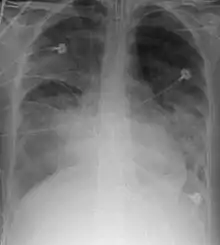

A chest X-ray showing right sided (seen on the left of the picture) pulmonary contusion associated with rib fractures and subcutaneous emphysema

Chest X-ray is the most common method used for diagnosis,[37] and may be used to confirm a diagnosis already made using clinical signs.[20] Consolidated areas appear white on an X-ray film.[42] Contusion is not typically restricted by the anatomical boundaries of the lobes or segments of the lung.[27][43][44] The X-ray appearance of pulmonary contusion is similar to that of aspiration,[32] and the presence of hemothorax or pneumothorax may obscure the contusion on a radiograph.[25] Signs of contusion that progress after 48 hours post-injury are likely to be actually due to aspiration, pneumonia, or ARDS.[10]

Although chest radiography is an important part of the diagnosis, it is often not sensitive enough to detect the condition early after the injury.[35] In a third of cases, pulmonary contusion is not visible on the first chest radiograph performed.[7] It takes an average of six hours for the characteristic white regions to show up on a chest X-ray, and the contusion may not become apparent for 48 hours.[7][27][43] When a pulmonary contusion is apparent in an X-ray, it suggests that the trauma to the chest was severe and that a CT scan might reveal other injuries that were missed with X-ray.[2]